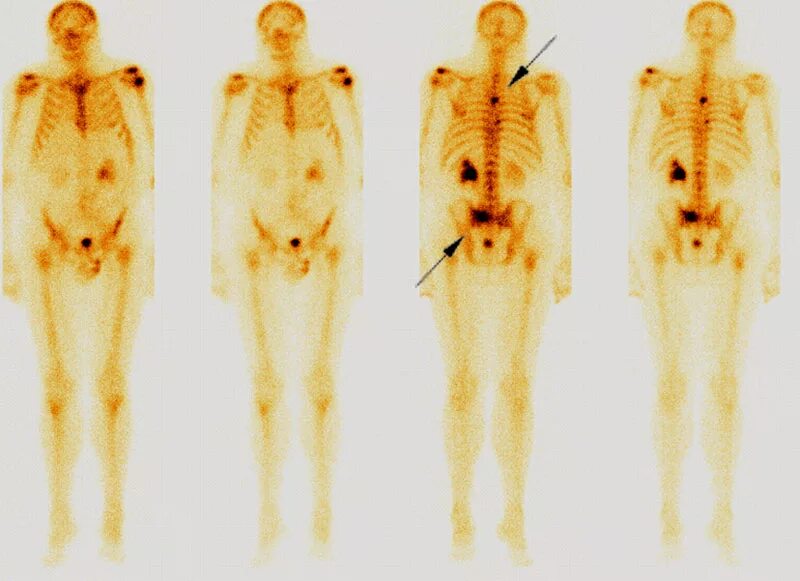

Метастазы скелета